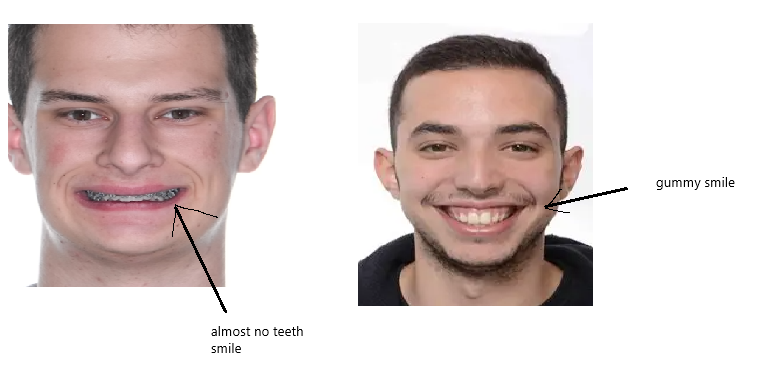

3. you have a gummy smile(impaction even if it comes some with downsides) or little tooth show( downgraft case, sfs)

4. you need to have bite issues, extreme overbite(7 mm +), underbite, deep bite, or anterior open bite(get your condyles checked).(you can create via decomp)

3. you have a gummy smile(impaction even if it comes some with downsides) or little tooth show( downgraft case, sfs)

4. you need to have bite issues, extreme overbite(7 mm +), underbite, deep bite, or anterior open bite(get your condyles checked).(you can create via decomp)